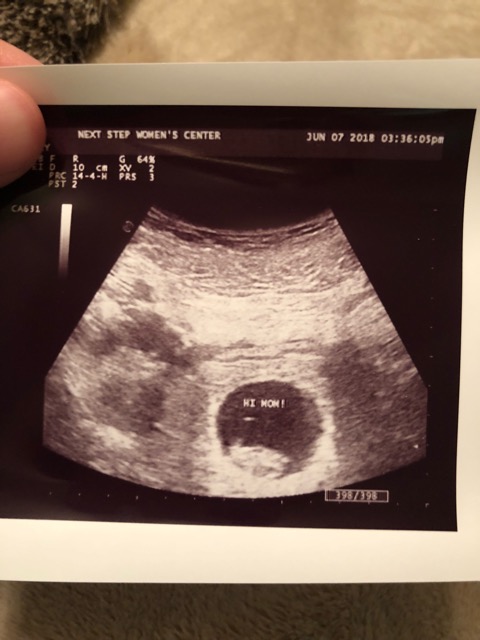

Boy or girl?

Trouble detecting where placenta is. This is done abdominally! What do you think it is?? Ramzi me!